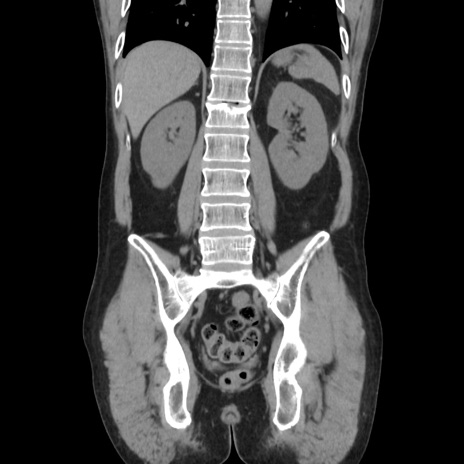

症例37(冠状断像)

【症例】40歳代 男性

【主訴】腹痛

【現病歴】4時間ほど前に電車に乗車中に臍部上より腹痛出現。徐々に増悪し起立困難となり、救急外来受診。生ものは数日食べていない。今朝お雑煮を食べた。

【身体所見】BT 36.8℃、BP 117/84mmHg、HR 91/min、SpO2 97%、苦悶様、腹部:臍上部広範囲圧痛あり、反跳痛±

【データ】WBC 8100、CRP 0.03